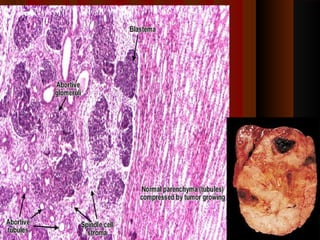

Wilms' tumor or nephroblastomaWilms' tumor or nephroblastoma

 Most common primary renal tumor of childhood (ages 2-5 years).Most common primary renal tumor of childhood (ages 2-5 years).

 It originates from renal blastema & has epithelial & stromal derivativesIt originates from renal blastema & has epithelial & stromal derivatives

MicroscopicallyMicroscopically

 These are generally known as the classic triphasic combination:These are generally known as the classic triphasic combination:

1) blastmemic - Nest & sheets of primitive blastema within1) blastmemic - Nest & sheets of primitive blastema within

mesenchymemesenchyme

 2) stromal - (straited muscle, smooth muscle, cartilage, bone, fat cells,2) stromal - (straited muscle, smooth muscle, cartilage, bone, fat cells,

collagen fibrous tissue, cholesterol crystals & lipid,)collagen fibrous tissue, cholesterol crystals & lipid,)

 3) epithelial - abortive tubules, abortive glomeruli,3) epithelial - abortive tubules, abortive glomeruli,

 Spindle cell stroma gives a sarcomatoid patternSpindle cell stroma gives a sarcomatoid pattern

MicroscopicallyMicroscopically  These aregenerally known as the classic triphasic combination:These are generally known as the classic triphasic combination: 1) blastmemic - Nest & sheets of primitive blastema within1) blastmemic - Nest & sheets of primitive blastema within mesenchymemesenchyme  2) stromal - (straited muscle, smooth muscle, cartilage, bone, fat cells,2) stromal - (straited muscle, smooth muscle, cartilage, bone, fat cells, collagen fibrous tissue, cholesterol crystals & lipid,)collagen fibrous tissue, cholesterol crystals & lipid,)  3) epithelial - abortive tubules, abortive glomeruli,3) epithelial - abortive tubules, abortive glomeruli,  Spindle cell stroma gives a sarcomatoid patternSpindle cell stroma gives a sarcomatoid pattern 3939